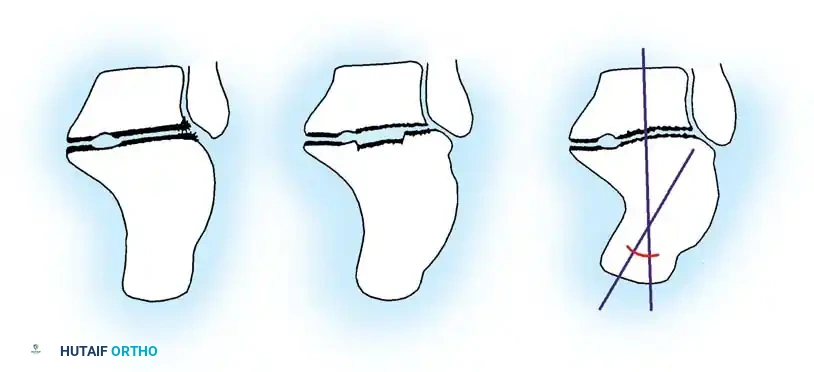

2. Calcaneal Osteotomy and Realignment Arthrodesis (Type II & III)

Intraoperative marking of the planned calcaneal osteotomy lines to correct varus/valgus malalignment.

Levering and distraction of the osteotomy site to restore calcaneal height and correct the talar declination angle.

The technique involves a lateral decompression, medial subtalar capsulotomy, and aggressive distraction of the subtalar joint. A lamina spreader is inserted to restore the talocalcaneal height.

Diagrammatic representation of subtalar distraction and realignment arthrodesis using a tapered wedge bone graft.

A tricortical iliac crest bone graft (or the resected lateral wall exostosis) is fashioned into a tapered wedge and impacted into the distracted subtalar joint. This bone block restores heel height, improves talar inclination, and corrects varus/valgus malalignment.